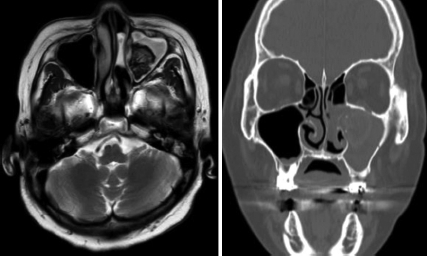

문 2. 77세 여자 환자가 좌측 비강 내 용종 및 부비동염으로 의뢰되었다. 이 환자의 외부병원 MR 및 CT 소견은 다음과 같다. 환자의 치료와 관련하여 옳은 것은?

① 우선적으로 항생제, 코세척 및 국소 스테로이드제 치료를 시도한다.

② 치료는 내시경을 이용해 균사덩어리를 완전히 제거하는 것이다.

③ 부비동 환기를 회복시켜 점액섬모운동이 회복되어도 재발할 수 있으며, 20% 이상에서 재발한다고 알려져 있다.

④ 진균구를 완전히 제거하기 위해 경하비도 개방술, 견치와 천자 또는 상악동 근치술이 필수적이다.

⑤ 수술 후 국소 또는 전신 항진균제 사용이 필요하다.

문 2. 답 ②

해 설 진균구 증례이며, 수술 후 국소 또는 전신 항진균제 사용이 필요하지 않다. 부비동 환기를 회복시켜 점액섬모운동이 회복되면 재발은 드물어 약 1% 이하에서 재발하는 것으로 보고되어 있다. 상악동의 구석에 존재하여 기구가 미치지 못하는 진균구는 강한 식염수세척으로 대부분 제거가 가능하다. 식염수세척에도 제거가 어려운 경우 경하비도 개방술, 견치와 천자 등의 방법을 병용할 수 있다.

참고 문헌: 대한이비인후과학회. 이비인후과학:비과. 개정2판. 파주: 군자출판사;2018. p.312-3.